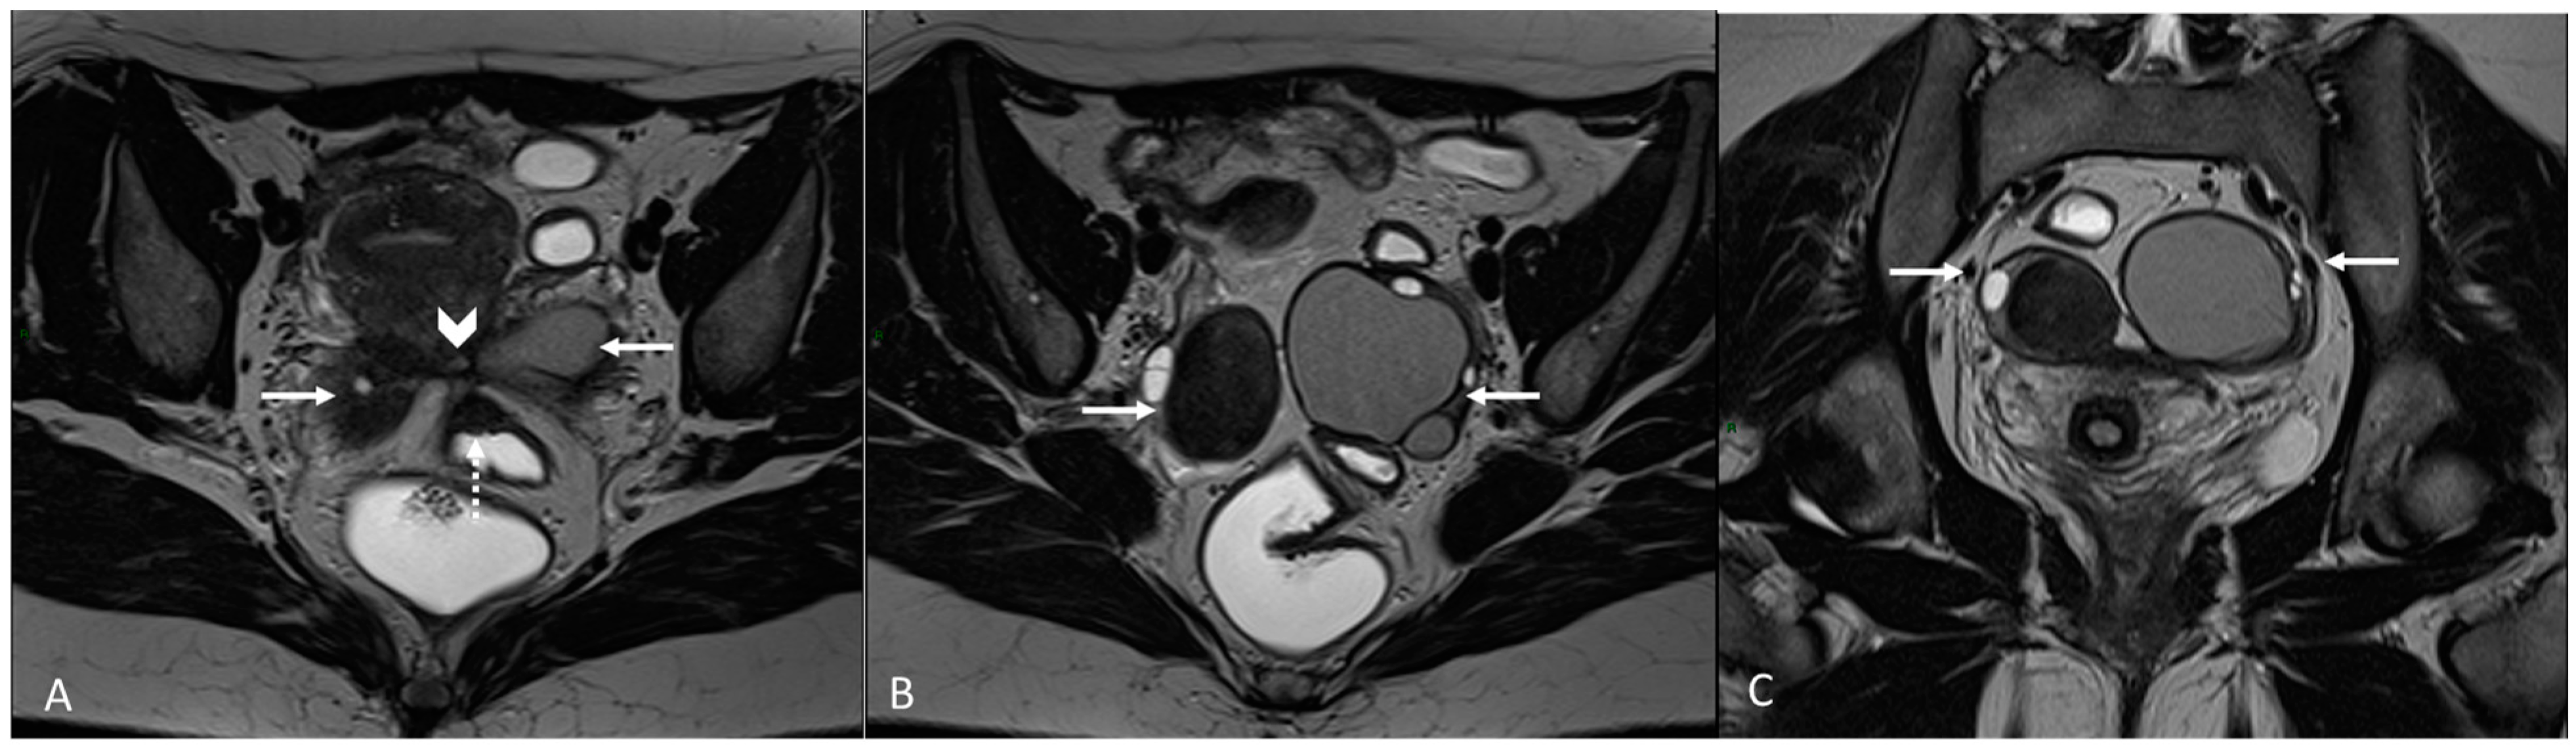

4. Ovarian Endometrioma

- Rousset, P.; Florin, M.; Bharwani, N.; Touboul, C.; Monroc, M.; Golfier, F.; Nougaret, S.; Thomassin-Naggara, I.; ENDOVALIRM Group. Deep Pelvic Infiltrating Endometriosis: MRI Consensus Lexicon and Compartment-Based Approach from the ENDOVALIRM Group. Diagn. Interv. Imaging 2023, 104, 95–112. [Google Scholar] [CrossRef]

- Kido, A.; Himoto, Y.; Moribata, Y.; Kurata, Y.; Nakamoto, Y. MRI in the Diagnosis of Endometriosis and Related Diseases. Korean J. Radiol. 2022, 23, 426–445. [Google Scholar] [CrossRef]

- Dias, J.L.; Veloso Gomes, F.; Lucas, R.; Cunha, T.M. The Shading Sign: Is It Exclusive of Endometriomas? Abdom. Imaging 2015, 40, 2566–2572. [Google Scholar] [CrossRef]

| Localization | MRI Sign | MRI Findings | |

| Ovary | Ovarian endometrioma | T1 high signal multiplicity | Multiple high signal cyst on T1WI |

| T2 shading | Marked gradation or shading on T2WI | ||

| T2 dark spot sign | Well-defined markedly hypointense foci within the cyst on T2WI | ||

| Ovary | Kissing ovary | Bilateral ovaries located on top of the uterus | |